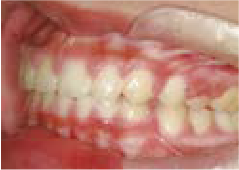

Jさん (矯正開始時:8歳)

Before

After

歯がガタガタに並んでいて、前歯の真ん中の位置が少し左にずれていました。

奥歯が生えるためのスペースが足りず、永久歯が生えて来られない状況が確認できました。

また、飲み込むとき下くちびるに力が入ってしまうクセが見られ、お顔全体の成長が遅れている様子が確認できました。

治療を終えて

歯がきれいに生えるためのスペースをしっかり確保することができ、歯並びを乱していたお口のクセも改善されたため、奥歯が生えるスペースを確保することができました。

しっかり噛めるかみ合わせを作ることが、将来の健康につながるので「よく噛む」練習も続けてもらっています。

主訴・治療内容 歯がガタガタになってきたことに悩み、無料相談に来院されました。

治療期間 3年

費用 462,000円(税込)